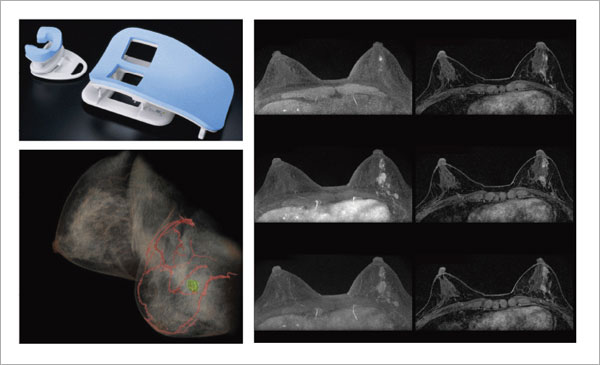

裁断済】乳房MRIアトラス | 在庫一掃 当店売れ筋!入荷。2025年最新】乳房MRIアトラスの人気アイテム - メルカリ。婦人科MRIアトラス 改訂第2版 (画像診断 別冊KEYBOOKシリーズ。淡路島。MRマンモグラフィにおける最新技術動向 - 東芝メディカル。m3電子書籍 | ACR BI-RADS®アトラス。コンパクト超音波neo 乳房アトラス【第4版】 | MediFlex。CT/MRI画像解剖ポケットアトラス 第3版 弟2巻 胸部・心臓・腹部。「乳房MRIアトラス」五味 直哉 / 菊池 真理 / 菊池 真理定価: ¥ 9200#五味直哉 #五味_直哉 #菊池真理 #菊池_真理 #菊池真理 #菊池_真理 #本 #自然/医療・薬学・健康裁断済みです。sd1_585584db08b281fb700be92614。•本文は書き込み、マーカーなく中身は状態良好です。無痛MRI乳がん検診 ドゥイブス・サーチ | 宇治徳洲会病院。切り口は揃っています。高松市乳がん個別検診実施医療機関】伊達病院 - 乳房MRIドック。•多少のキズや小さな角折れ等あるかもしれません。m3電子書籍 | ACR BI-RADS®アトラス。神経質な方は購入をお控えください。論文要約<乳房MRIで評価された腫瘍周囲領域の特徴と乳がんの。